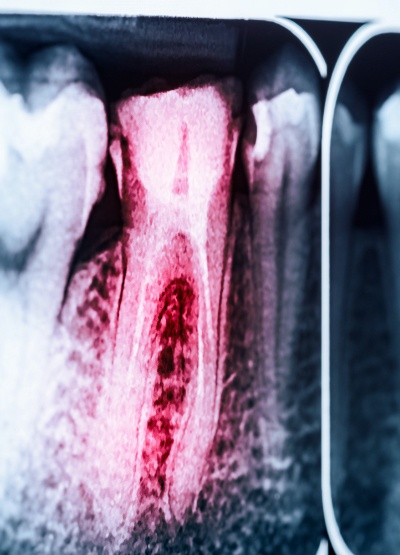

Root Canal

Tooth decay can be treated, but if left alone it will eventually reach the pulp at the center of the tooth. The pulp contains the nerve system of the tooth, meaning it will cause a lot of discomfort if it becomes infected. The damage will only become more severe, but root canal therapy allows us to stop the pain and save the tooth. We simply remove the pulp and other infectious material before filling the tooth back up with a biocompatible substance.

Learn More About Root Canal Therapy